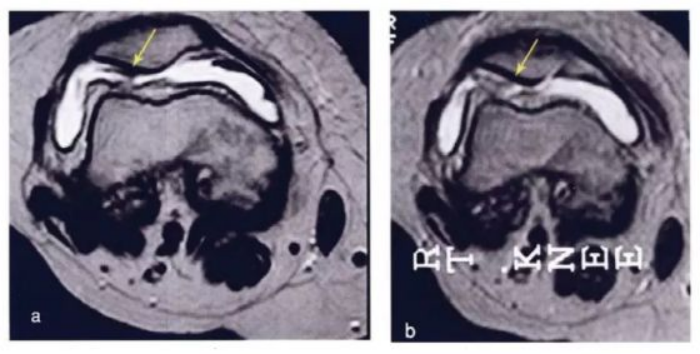

·研究结果:关节内注射骨髓间充质干细胞6个月后,疼痛、功能状态和步行距离均提高。6名治疗组中3名患者在治疗前后的MRI比较可以看出,该治疗对于改善软骨厚度,修复组织延伸超过软骨下骨,以及减少软骨下骨的水肿是非常显著的。

下图a示意治疗前软骨,b为治疗后6个月软骨,箭头所示为软骨修复位置。